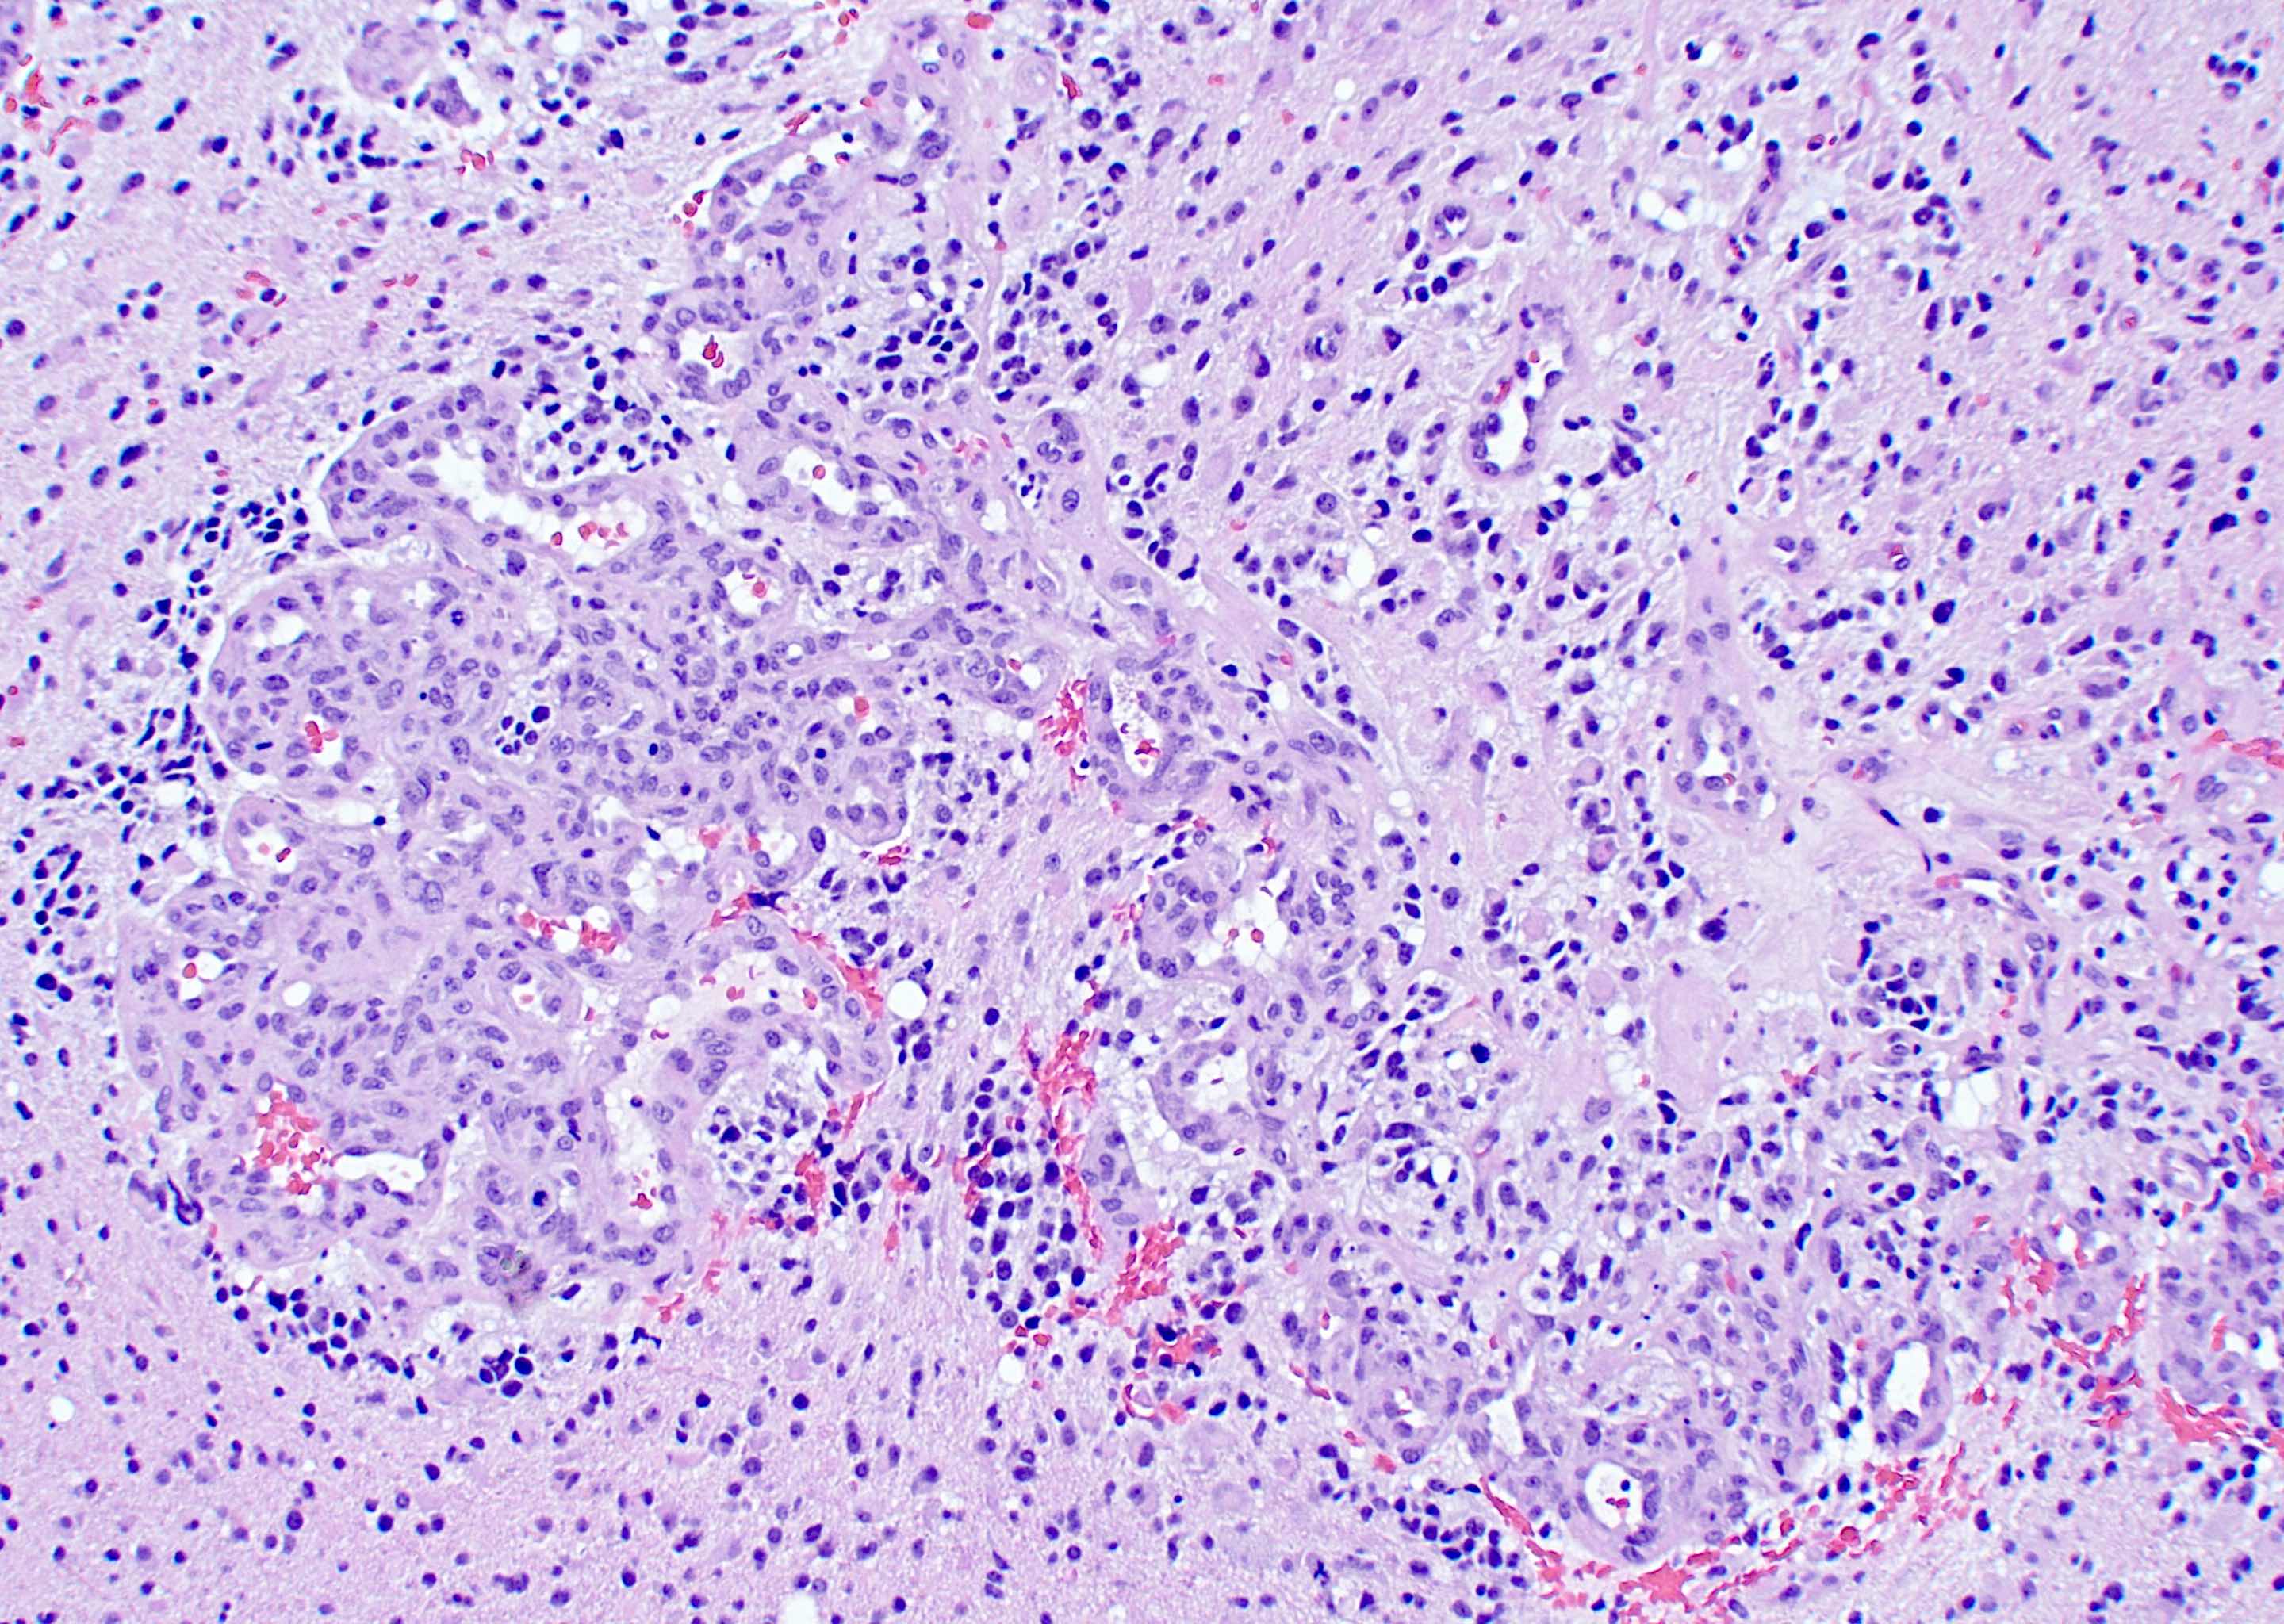

Translational Proteomics in Glioblastoma

Leveraging high-resolution proteomic profiling, we explore the biologic heterogeneity of glioblastoma, identify mechanisms of therapeutic resistance, and define actionable biomarkers to guide precision neuro-oncologic therapies. Our research links molecular signatures with clinical and surgical variables to enable rational trial design and improved patient stratification.